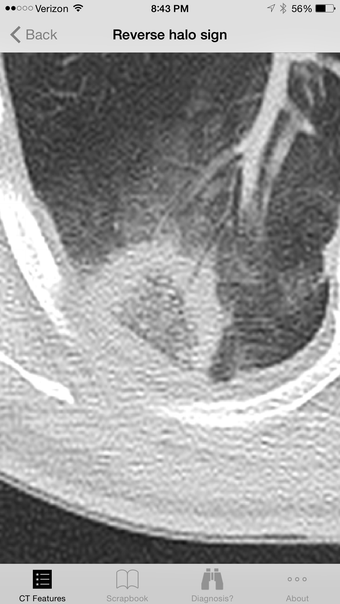

Lung CT Field Guide 应用程序是一种宝贵的资源,专为各种医师专家设计,特别是放射科医师和肺科医师。这一教育工具通过提供详细的影像学发现和常见肺部疾病的彩色图形插图,帮助解释肺部 CT 扫描。用户可以查看超过 100 张精心挑选的 CT 图像和插图。该应用程序还配备了一个实验性诊断引擎,根据观察到的肺部 CT 发现生成不同诊断列表,提升各个级别医疗专业人士的教育体验。

适用于医务人员、住院医师、住院医师和医学生,Lung CT Field Guide 应用程序提供了大量的肺部 CT 图像和图形插图,使其成为一种无与伦比的价格点下不可或缺的工具。